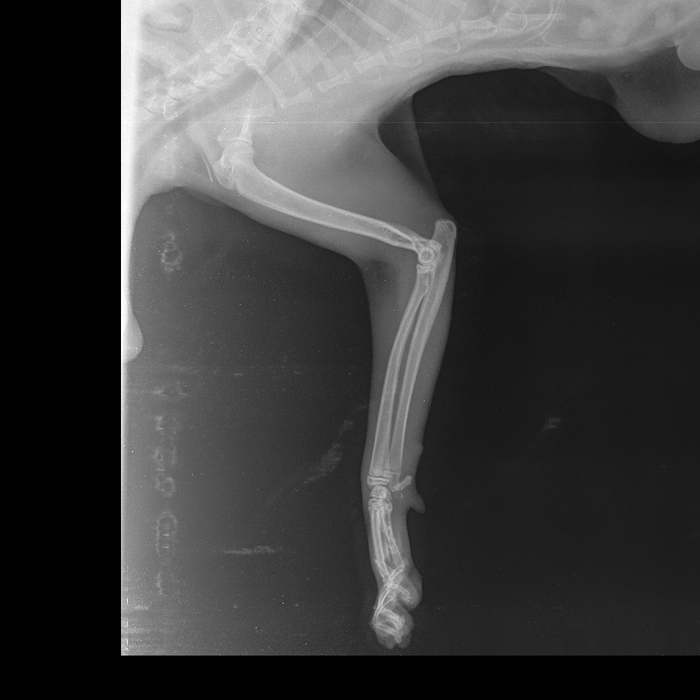

2 августа эта красота решила отметить праздник. Отодрала сетку с балконного окна и сиганула с 5 этажа без парашюта (скорее всего голуби радразнили). Дома никого не было. Судя по всему приземлилась на газон, доковыляла до околопод'ездной лавочки и дождалась меня. -1 кошачья жизнь, контузия правого легкого, ушиб двух правых лап, обошлось без переломов.